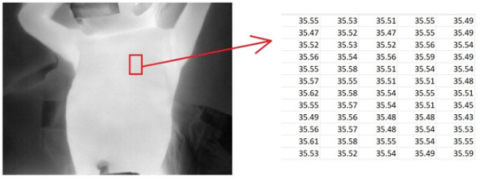

2.2 Thermal map

The temperature map is two-dimensional arrays that directly represent the temperature values of the thermograms. When these temperature values are normalized and displayed, a gray-level image is obtained as in Figure 3, where the white and black parts represent hot and cold regions, respectively.

Figure 3. Gray-level image and temperature map of the selected region